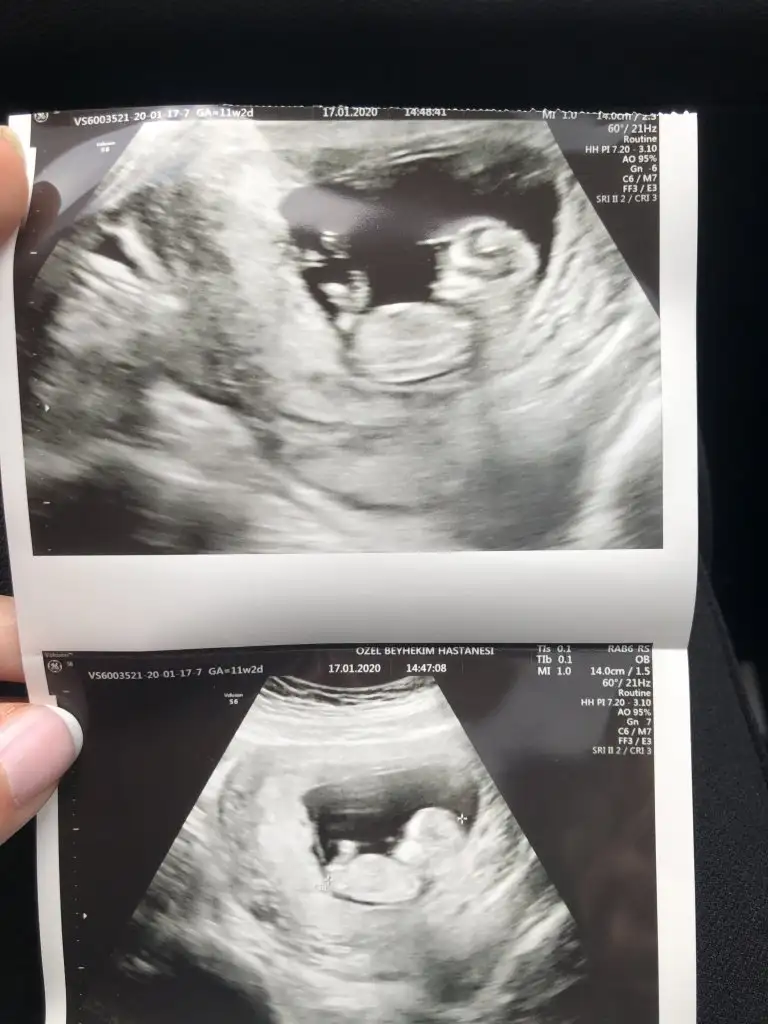

11+6 yorumlarsan sevinirim 😂bu arada doktor birşey söyledi ama net değil.

Benim de 11+6 😍🧿 bana da yorum yapar mısın? Ikra meyra Ikra meyra